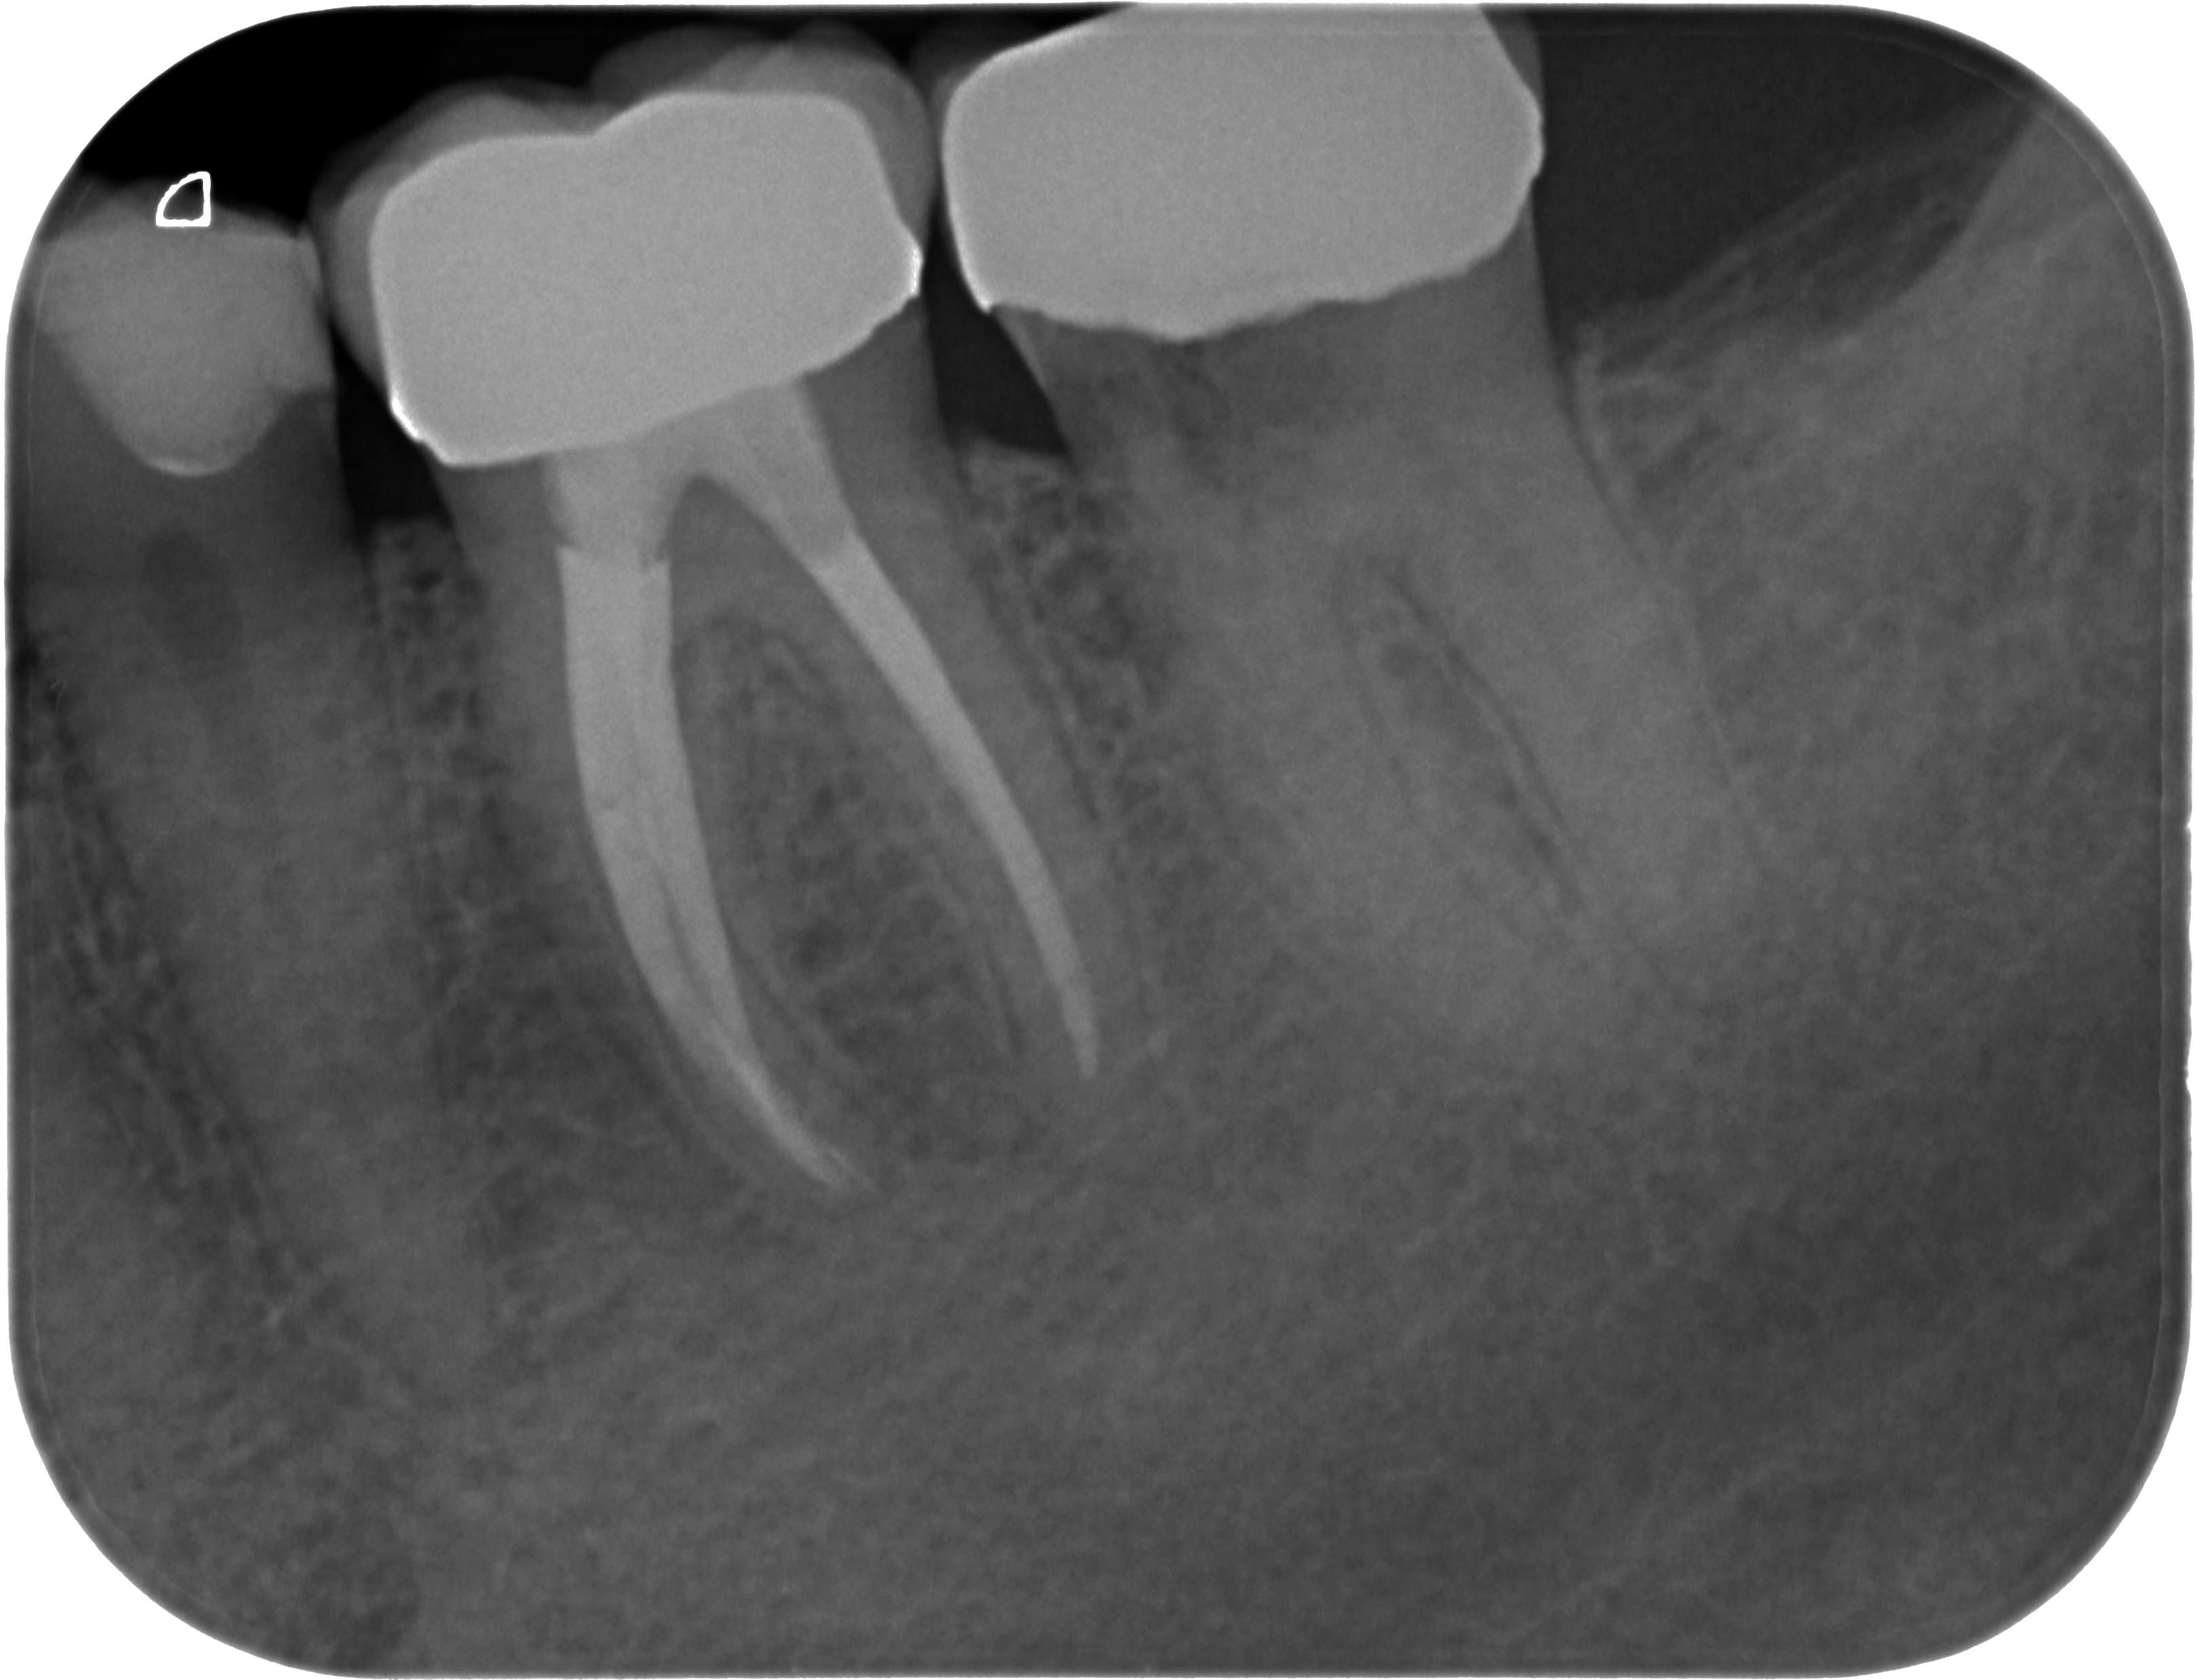

Resorption-1-3 Veröffentlicht 10. Juni 2013 am 3235 × 2474 in Was zeigt das DVT (4) ? Die Fälle Zahn 36,37